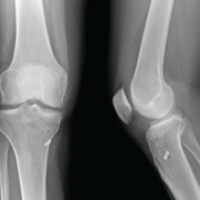

Radiological findings

X-rays revealed thin femur and tibial diameters on the affected side compared to the contralateral limb (Fig. 1).

Figure 1: X-ray of bilateral hip with pelvis with femur to compare femoral width between poliotic (L) and non-poliotic limb (R).